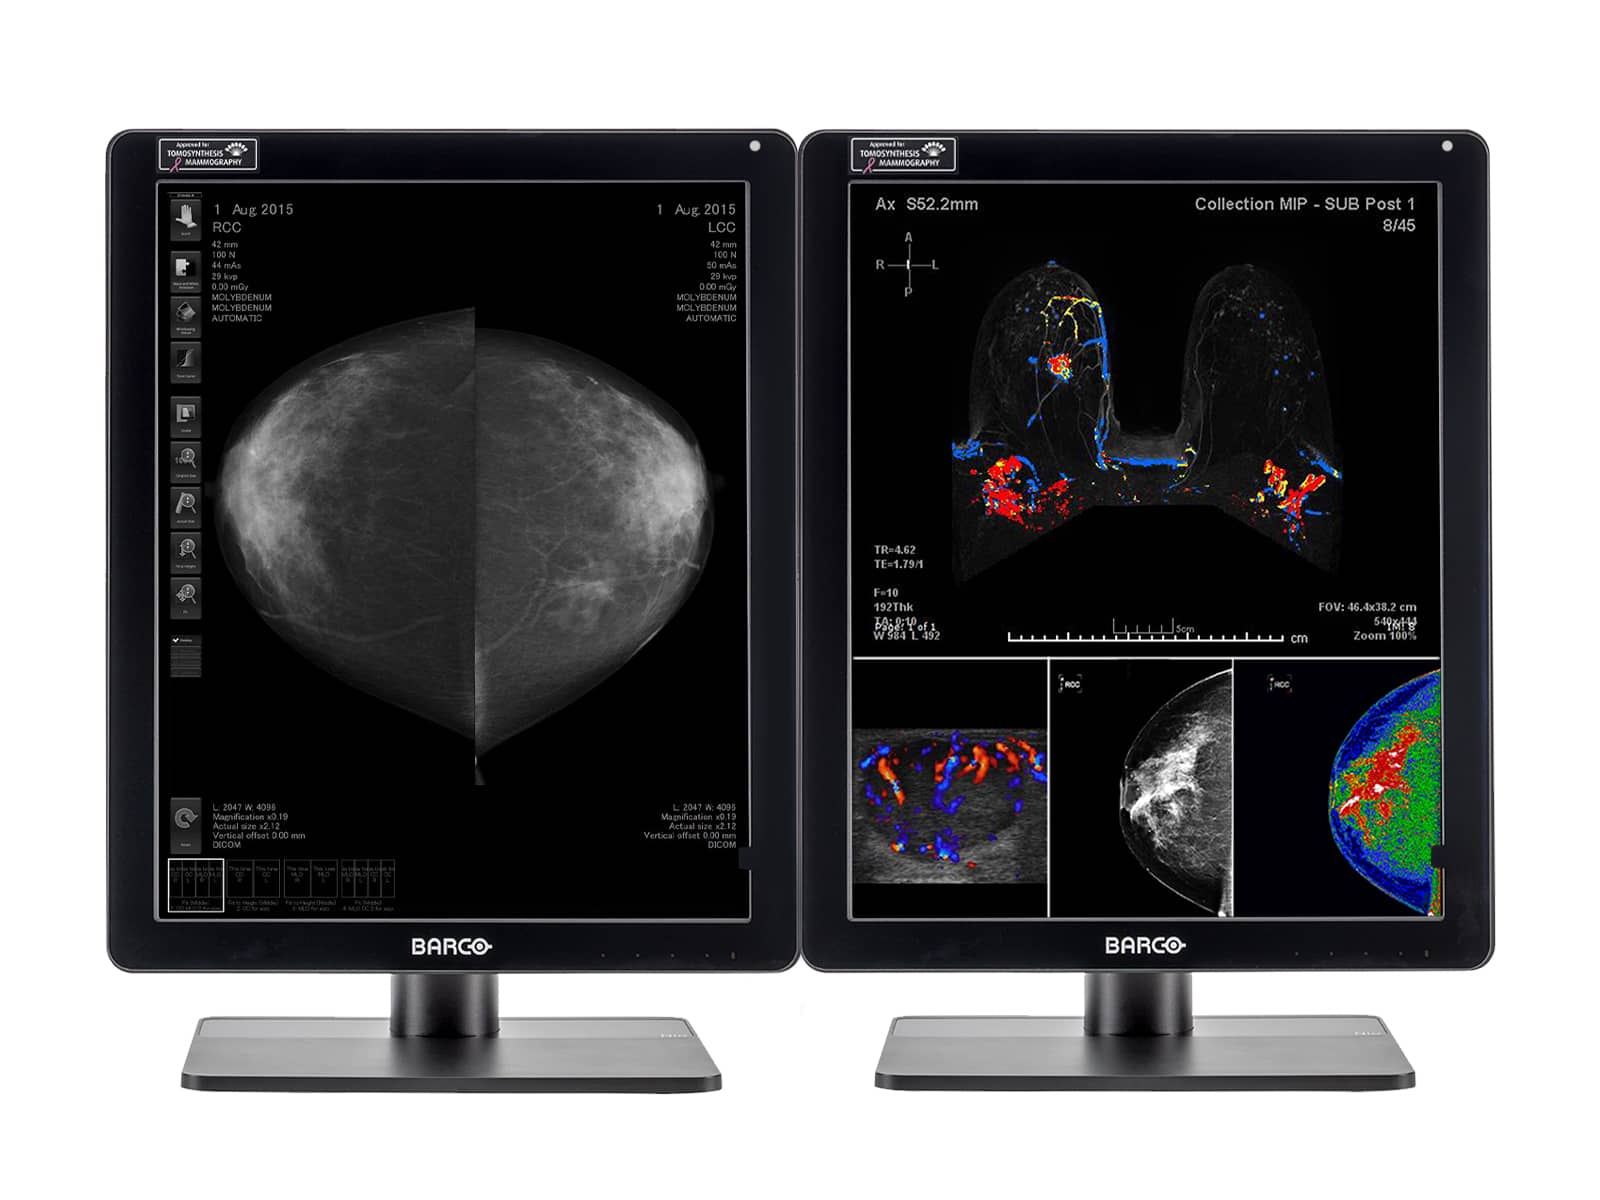

Barco Nio Fusion MDNC-12130 12MP 31" Color Tomosynthesis 3D-DBT Mammography Display

Barco Coronis UNITI MDMC-12133 12MP 33" Tomo Color LED Mammo 3D DBT PACS Display